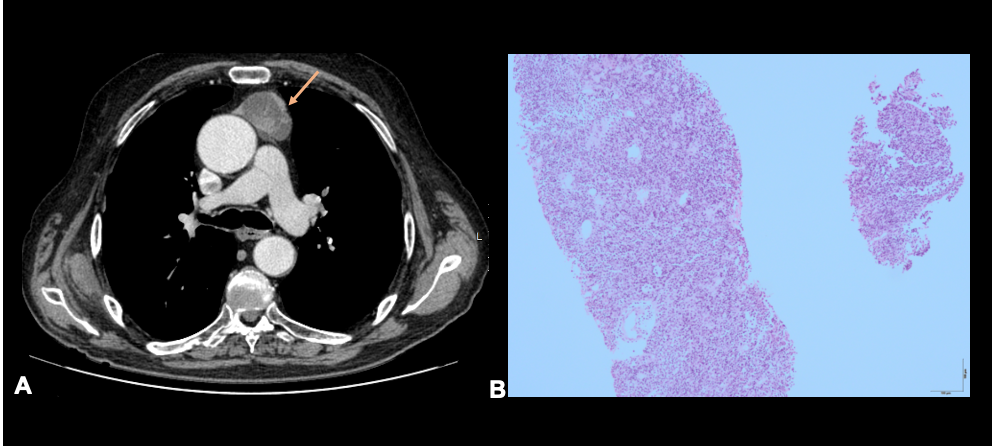

胸腺瘤在CT上通常表现为边界锐利、椭圆形的均质软组织肿块(图11-14)。偶尔,大的肿瘤可能显示钙化,出血区域,甚至坏死(图15)。局部浸润性疾病表现为不规则的肿瘤界面、胸膜结节和积液以及“滴状转移”[2]。

Thymomas in CT usually appear as a homogenous soft tissue mass with sharp borders and an oval shape (figures 11-14). Occasionally, large tumors may reveal calcifications, areas of hemorrhage, or even necrosis (figure 15). Locally invasive disease is suggested by irregular tumor interfaces, pleural nodules and effusion, and “drop metastases” [2].

901535.jpg

图11:男性,80岁。前纵隔结节性病变,边界清楚,不均匀,壁和间隔厚,并伴有一些囊性低密度(橙色箭头)。显示有血管结构和胸壁的交界面。光镜显示上皮细胞群无细胞异型性,混合有大量淋巴细胞。无坏死。形态学特征和免疫组织化学特征与胸腺瘤一致(H&E,100x)。

Fig 11:Male, with 80 years old. A- Nodular lesion in the anterior mediastinum with well-defined margins, heterogeneous, with thick wall and septa, and also with some cystic attenuation (orange arrow). It shows a cleavage plane with the vascular structures and thoracic wall. B- Photomicrograph reveals a population of epithelial cells without cytologic atypia, admixed with abundant lymphocytes. Necrosis is absent. Morphological aspects and immunohistochemical profile are compatible with thymoma (H&E, 100x).